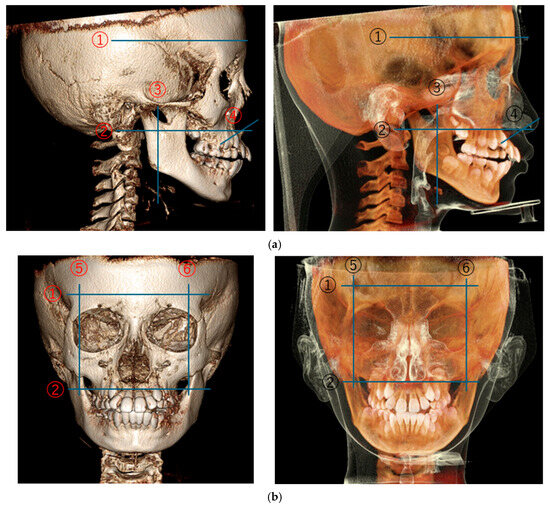

CBCT Volumetric Changes in Combined Nasal Cavity and Paranasal Sinuses Following RAMPA-ROA Therapy: A Retrospective Cohort Study with Reference to Longitudinal Growth Data

Background: The interrelationship between craniofacial morphology and respiratory function is a central focus of orthodontic and dentofacial orthopedic research. This study aimed to evaluate the volumetric changes in the sinonasal complex (combined nasal cavity and paranasal sinuses) following Right Angle Maxillary Protraction Appliance (RAMPA) therapy using cone-beam computed tomography (CBCT) and to compare these outcomes with established longitudinal growth benchmarks. Methods: A retrospective cohort analysis was conducted on 60 pediatric patients (24 males, 36 females; mean age: 86.60 ± 24.22 months) with radiologically clear paranasal sinuses at baseline (T1). Participants underwent RAMPA therapy for an average of 8.38 months. Volumetric quantification of the entire sinonasal complex—including the nasal cavity and all four paranasal sinuses (maxillary, ethmoid, sphenoid, and frontal)—was performed to ensure methodological alignment with existing normative growth data. Results: Total sinonasal volume increased significantly from 27,741.63 ± 10,675.85 mm3 at T1 to 32,248.00 ± 10,084.07 mm3 at T2 (p < 0.001), representing a mean gain of 4506.37 mm3 (16.24%). Notably, the annualized growth velocity under RAMPA therapy (6453 mm3/year) exceeded the physiological increment of age-matched normative data (~5418 mm3/year) by approximately 1.2 times. Despite a constricted baseline at T1 compared to normative values, the treatment group demonstrated a rapid “catch-up” growth trajectory. Conclusions: RAMPA therapy induces rapid and significant volumetric expansion of the sinonasal complex in pediatric patients, demonstrating a potent “acceleration effect” that surpasses natural physiological maturation. These findings suggest that orthopedic midfacial remodeling can effectively restructure the upper respiratory environment, bridging the gap between pathological constriction and normative developmental benchmarks in patients with maxillary hypoplasia.